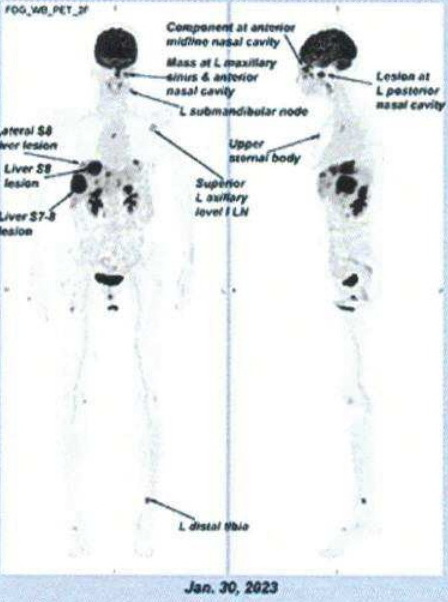

On 30th ,Jan. 2023, it was assessed that the number of intrahepatic metastasis increased, and the Hong Kong Sanatorium & Hospital estimated that the survival time was not long, and the patient was transferred back to Shenzhen for treatment.